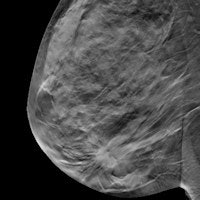

Digital breast tomosynthesis

Digital breast tomosynthesis has had a remarkable run as radiology's Hottest Clinical Procedure in the Minnies, winning the category for five years in a row, from 2010 to 2014, until it was dethroned by CT lung cancer screening last year.

Tomosynthesis is back in the mix in 2016, however, perhaps reflecting growing clinical evidence that supports the effectiveness of the technology (a study on tomosynthesis is also a candidate for Scientific Paper of the Year, below). Research studies in 2016 focused on using the 3D mammography technique in a screening role, where it has shown the ability to detect more cancers while recalling fewer patients. It has also shown promise in countering x-ray mammography's historic Achilles' heel in dense breast tissue.

Particularly intriguing is the idea of synthesized tomosynthesis, in which a 2D image is created from 3D tomo data. Such synthesized 2D images would obviate the need to acquire separate conventional mammography to accompany the 3D data, reducing the amount of radiation delivered during a tomo exam. Indeed, Pennsylvania researchers validated the technique in a study published in Radiology in July.